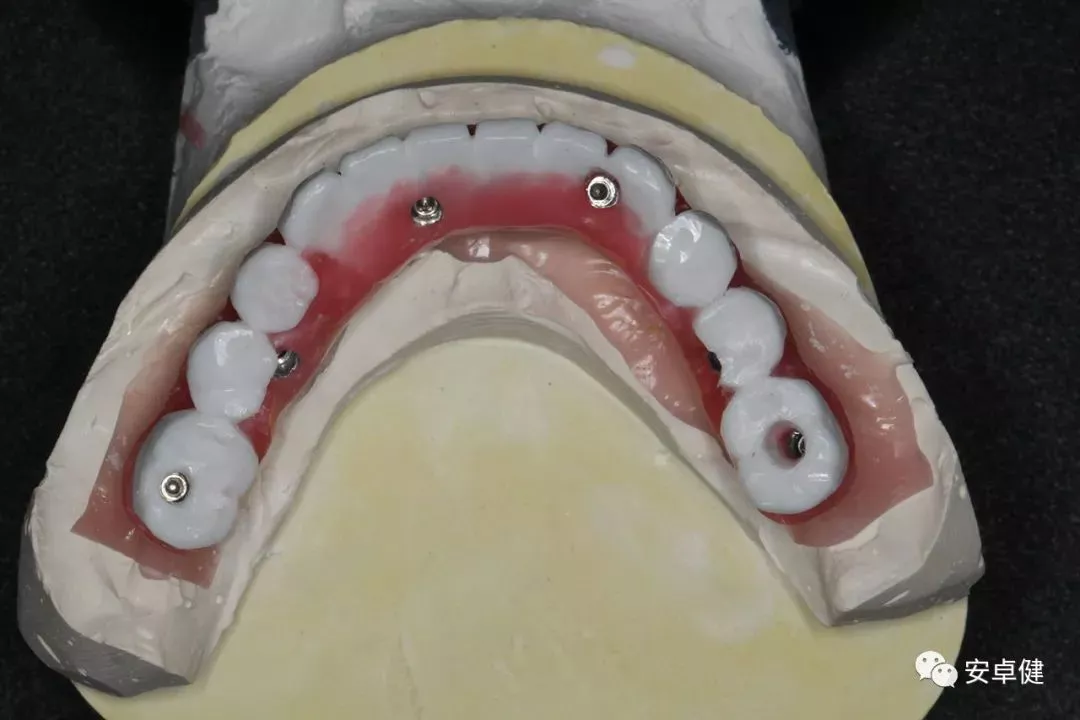

▷ 技工室制作

• 术后即刻制取印模后灌注石膏模型;

制作石膏模型

• 蜡型排牙于架就位,检查咬合及外形;

模型上架

• 由于疫情原因,术后16个月制取最终修复体印模;

最终修复体蜡型合面照

• 制作最终修复体蜡型,分别于架及口内试戴检查其外形及咬合;

• 完成最终修复体制作。

最终修复体合面照

在该病例中选择拔除患者无保留价值的下颌余留残根,在原有义齿的基础上,采用经数字化设计,计划在下颌植入6枚种植体,支持下颌一体式全口固定式修复方案。